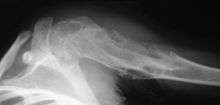

Ollier disease carries a high risk of skeletal, visceral and brain malignancy which occurs in approximately 25% of patients. Regular systemic screening is recommended.[5] Juvenile granulosa cell tumour has been associated with the disease.[6] The incidence of secondary chondrosarcoma in Ollier disease is not known, but may be as high as 25%, pelvis and shoulder girdle being the commonest locations.[4] A related disorder called Maffucci syndrome named after Angelo Maffucci is characterized by enchondromas associated with multiple hemangiomas which usually occur in the hands and feet. Maffucci syndrome carries a higher risk for cancer.